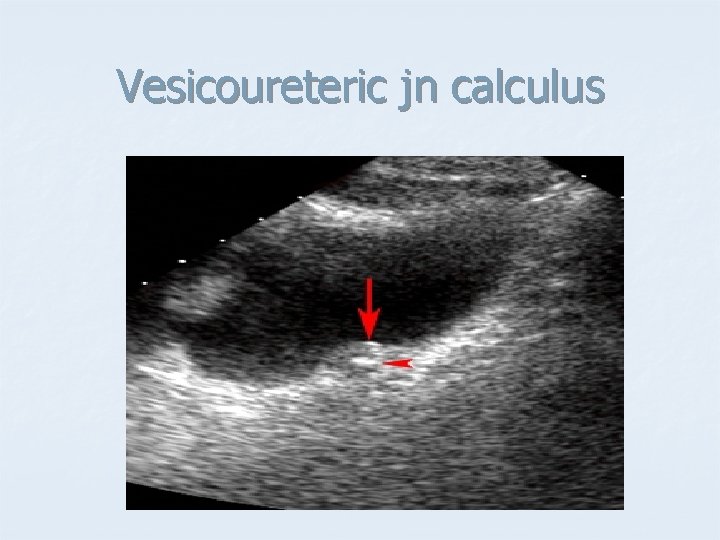

Vesicoureteric jn calculus